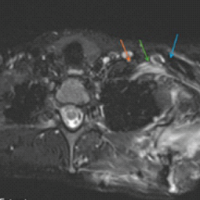

After the surgical site was prepared and draped, the CTVS team performed thoracoscopy through three portals to visualize the displaced fracture and any adhesions (Fig. 3).

Figure 3: Video-assisted thoracoscopy through 3 portals.

They meticulously removed the adhesions while protecting the underlying vital structures (Vid). A 6–-8 cm straight incision was made over the fracture site, which was opened in layers to access the fracture. After cleaning the fracture ends, we encountered difficulty in reducing the fracture due to the inability to use forceps or retractors. Consequently, we opted to place a 3.5 mm Schanz screw in the proximal fragment and applied traction with a periosteal elevator to facilitate reduction under thoracoscopic guidance (Fig. 4).